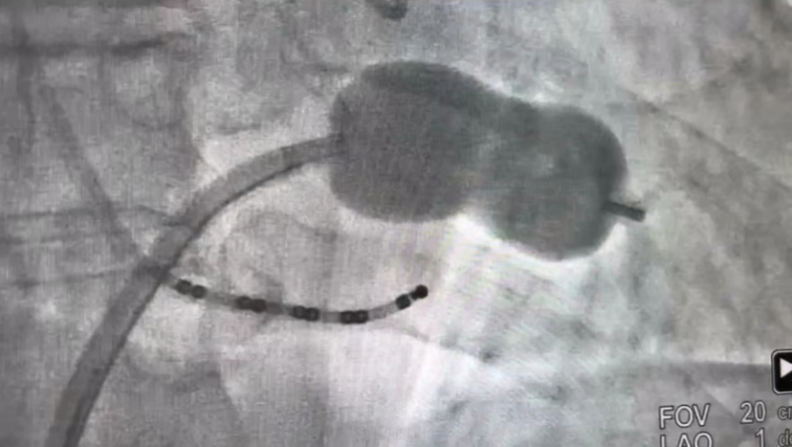

手术在介入导管室实施,李波团队在心脏超声科医师耿鑫术中监护、介入导管室护士、技师配合下完成。患者局部麻醉,穿刺右股静脉,行房间隔穿刺,送入二尖瓣扩张球囊至二尖瓣处,通过扩张球囊解除二尖瓣狭窄,术中心超测二尖瓣瓣口面积2.13cm2,轻度反流,瓣口面积大于1.5cm2即达扩张目的,提示该患者二尖瓣瓣膜扩张满意。经皮左心耳封堵术与二尖瓣球囊扩张术为同一手术路径,遂交换左心耳封堵器输送鞘,成功植入左心耳封堵器。既解除了患者二尖瓣狭窄,又能降低发生脑卒中风险。